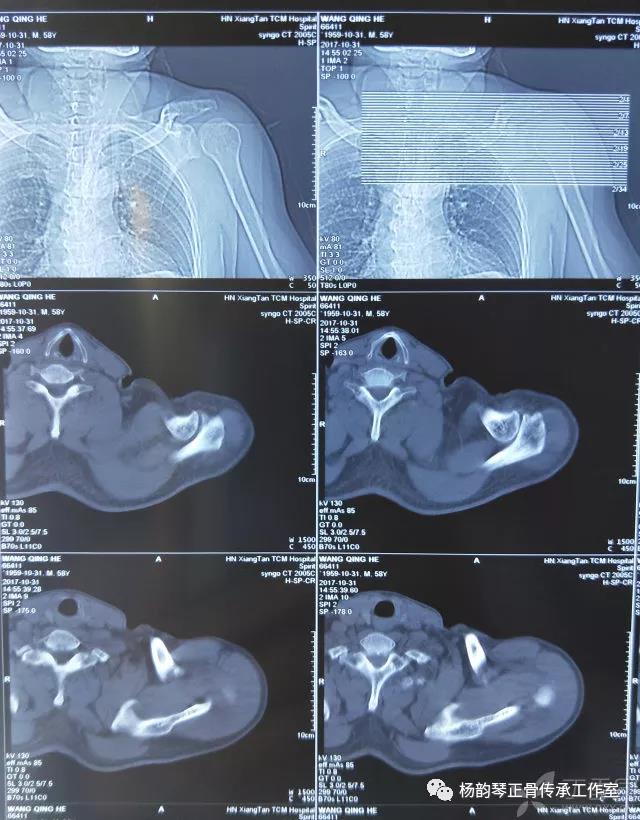

就诊我院后完善CT,诊断明确——左肩关节后脱位:

予以手法复位后拍片复查显示“灯泡征”消失,复位成功。讨论:肩关节后脱位在临床较为少见,特别是影像科经验不足很容易漏报,所以我们临床医生一定要自己仔细阅片,同时要结合体查来进行诊断,防止漏诊。肩关节后脱位时体查也有明显特征:肩关节前方明显变平,喙突较平时明显凸起容易触及,而肩关节后方明显丰满,上臂一般处于内旋内收位,无法主动外旋外展。肩关节后脱位的手法复位相对于前脱位的复位来说也比较容易。患者一般可以取坐位,助手自患侧腋下环抱患者稳定患者躯体,术者一手拉患肢上臂稍牵引内旋,一手自后方推顶肱骨头一般可以复位,如果单纯推顶无法复位也可以术者两手握住伤肢缓慢外展并沿肱骨纵轴牵引,然后逐渐外旋上臂即可复位。整复完成后可以把持患肢作肩关节各个方向的小幅度被动活动,防止肩关节粘连,肩关节后脱位的固定方法与肩关节前脱位的固定方法不同,应将患肢置于上臂外展、后伸、外旋位固定,即外展30度、后伸30度和轻度外旋位,用外展支架固定3周后,循序渐进开始肩关节功能康复。